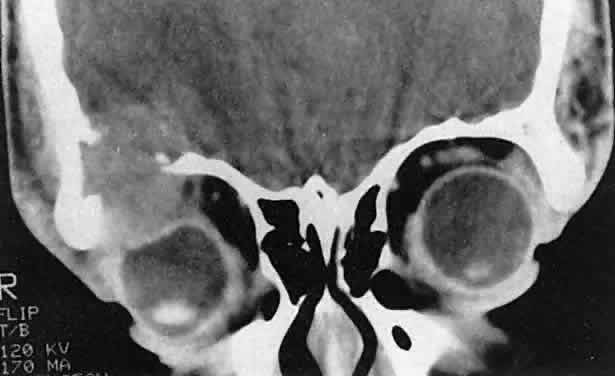

Although no single regimen is appropriate for every child with orbital rhabdomyosarcoma, a sample protocol might include multiple 3-week cycles of chemotherapy, each beginning with intravenous vincristine, actinomycin-D and cyclophosphamide, with vincristine repeated on the eighth and fifteenth days of each cycle. The regimen might include external radiation to a total dosage of 5040 cGy. For poor prognosis cases (e.g., metastatic alveolar rhabdomyosarcoma), newer agents under investigation include ifosfamide, etoposide, and topotecan.2 Having made the diagnosis and contributed to local staging at the time of presentation, the orbital surgeon continues to follow the patient along with the pediatric oncology team. In cases of treatment failure, “salvage” surgery may take the form of orbital exenteration8 or excision of residual tumor combined with brachytherapy.9 Rhabdomyosarcoma underscores the importance of clinical suspicion when dealing with acute proptosis in childhood. Prompt referral to a tertiary center after appropriate imaging is the responsibility of the primary ophthalmologist, family practitioner, or pediatrician who may first encounter the patient. OTHER PRIMARY SARCOMAS Other primary orbital sarcomas may have a relatively abrupt onset of proptosis, although their progression generally is less explosive than that of rhabdomyosarcoma. As with rhabdomyosarcoma, a prompt biopsy is critical for appropriate management. Alveolar soft part sarcoma, an example of this group of lesions, is a rare tumor that may affect the pediatric orbit. In an extensive review of the literature, Sullivan and colleagues10 identified about 50 orbital cases. They noted that the tumor tends to involve the extremities of young adults or the head and neck region of children, with a predilection for the orbit and tongue. A myogenic origin is favored, but there also is evidence for a neural derivation. The findings of imaging studies are nonspecific. Diagnosis depends on the light and elec-tron microscopic demonstration of periodic acid-Schiff-positive, diastase-resistant crystals within the cytoplasm of large polyhedral tumor cells.11 Pediatric patients appear to have a better prognosis than do adults. The currently recommended treatment is local excision of circumscribed primary lesions, with exenteration reserved for diffuse orbital involvement or local recurrence. Radiation therapy may have adjunctive value. Epithelioid sarcoma is a rare tumor that can occur in older children and young adults. Most lesions originate in the distal upper extremities. White and coworkers12 identified two patients; one was a 17-year-old girl with primary epithelioid sarcoma of the orbit. The tumors have both mesenchymal and epithelial histologic qualities and grow in tendon sheaths in a grossly nodular pattern. Treatment strategies have yet to be defined for this rare lesion. NEUROBLASTOMA Neuroblastoma is the most common metastatic orbital lesion in children.13 It represents 10% to 15% of all pediatric malignancies, ranking behind only leukemia and solid central nervous system tumors in frequency. It is a tumor of primitive neuroblastic tissue and, in some respects, is the autonomic nervous system counterpart of retinoblastoma. It usually originates in the adrenal medulla or other retroperitoneal sites but also may arise from any of the sympathetic ganglia in the mediastinum or neck. Neuroblastoma typically afflicts children from 18 months to 3 years of age, although it may be present at birth or may not appear until the midteens. In a review of more than 400 cases of neuroblastoma, Musarella and colleagues14 found the incidence of ophthalmologic signs to be 20%. In almost half of these cases, the ocular symptoms were the presenting complaints. The most common eye signs were related to orbital metastasis. Orbital involvement was bilateral in approximately half of the cases. Characteristic eye findings include proptosis and periorbital ecchymosis. The latter results from hemorrhagic necrosis within a rapidly growing tumor that has outstripped its blood supply. Other eye signs may reflect more distant tumor involvement. Horner's syndrome can result from a primary neuroblastoma in the sympathetic ganglia of the neck or mediastinum or from metastases to either of these regions.13–15 An infantile Horner's syndrome is characterized by hypochromia of the ipsilateral iris. Ocular signs may include opsoclonus, a wild conjugate oscillation of both eyes that may be associated with myoclonus, and truncal ataxia.14 It has been proposed that this complex results from an antibody directed against neuroblastoma antigen, which may cross-react with cerebellar tissue, producing damage in that area.16 Neuroblastomas manufacture catecholamines, which, in sufficient quantity, can produce flushing, systemic hypertension, and diarrhea. Diagnosis is aided by the demonstration of catecholamine metabolites in the urine.17 In cases of suspected neuroblastoma metastatic to the orbit, the primary tumor may be shown by abdominal or thoracic imaging studies. A histologic diagnosis generally is required, however. Orbital soft tissue involvement usually follows extension from bony metastasis (Fig. 3). Therefore, orbital biopsies should be performed extraperiosteally, because the periorbita may still be intact and constitute a relative barrier to tumor extension. Because the histologic differential diagnosis includes other poorly differentiated tumors of childhood, speci-mens should be fixed in both formalin and glutaraldehyde, and fresh tissue also should be submitted. Histologically, neuroblastomas display features commensurate with their degree of differentiation. At the more primitive end of the spectrum are tumors comprising small round cells with minimal cytoplasm. At the other extreme are lesions consisting of large, cytoplasm-rich elements resembling ganglion cells. It has been proposed that neuroblastomas having undergone spontaneous clinical regression have evolved into benign ganglioneuromas.18 Homer-Wright pseudorosettes characteristically present in well-differentiated primary neuroblastomas and are rarely, if ever, found within orbital metastases. In poorly differentiated tumors, electron microscopy may be required to show neurosecretory granules containing catecholamines. The rapidly advancing field of immunohistochemistry also has contributed to diagnosis and prognostic assessment in neuroblastoma.19 As with rhabdomyosarcoma, the choice of treatment protocols for neuroblastoma is based on tumor staging and the multiple prognostic factors that have been identified in large cooperative trials. Approximately 25% of children with newly diagnosed neuroblastoma present with nonmetastatic and localized disease.19 This group has a 98% survival with surgery alone as primary therapy. However, children with localized disease who have amplification of the MYCN oncogene or who are 2 years of age or older with either unfavorable histopathology or positive lymph nodes are at greater risk of death. Other negative factors include elevated serum ferritin and elevated serum neuron-specific enolase. The majority of children with neuroblastoma have metastatic disease at diagnosis.20 In order of frequency, the most common sites are bone marrow, bone, lymph nodes, liver, intracranial and orbital sites, lung, and central nervous system. The metastatic pattern differs with age. Patients younger than 1 year are more likely to have liver or skin metastases at diagnosis and less likely to have bone and bone marrow metastases at diagnosis than do patients age 1 year or older. Among children with metastases at diagnosis, event-free survival is decreased in patients with bone, bone marrow, central nervous system, intracranial/orbital, lung and pleural metastases, and improved in those with liver and skin metastases. Depending on tumor staging and risk factors, treatment protocols may include surgical resection of the primary tumor, combination chemotherapy (cisplatin, cyclophosphamide, doxorubicin, and etoposide) of varying dose-intensity, and myeloablative therapy with autologous purged bone marrow transplantation.19 OTHER METASTATIC LESIONS Orbital metastases from other solid pediatric tumors are less common. Of these, Ewing's sarcoma accounts for the majority, and Wilms' tumor is responsible for an extremely small number of cases.13,21 Ewing's sarcoma accounts for approximately 10% of tumors that metastasize to the pediatric orbit. Albert and colleagues13 noted orbital involvement in five of 12 patients with Ewing's sarcoma. In all patients, the orbital metastases were unilateral and were clinically noted several months after diagnosis of the primary lesion. Ewing's sarcoma usually arises within the medullary canals of the bones of the trunk or extremities. Unlike neuroblastoma, its peak incidence is in late childhood and adolescence. Ewing's sarcoma and malignant peripheral neuroectodermal tumor (PNET) are closely related, but are distinguished by the microscopic and immunohistochemical findings of greater neuroectodermal differentiation (e.g., rosette formation) in the latter lesion.22,23 Although earlier studies suggested a poorer prognosis in PNET than in Ewing's sarcoma, more recent work showed no difference in clinical outcome.24 Radiation therapy, surgery, and chemotherapy are used in management. The principal adverse prognostic factor is metastasis at diagnosis. In a European study of 975 patients enrolled from 1977 to 1993, the 5-year relapse-free survival of patients without metastases at diagnosis was 55% compared to 22% for patients with metastases at diagnosis.25 During the second 8 years of the study, these figures were 60% and 30%, respectively, indicating continued outcome improvement. Wilms' tumor (nephroblastoma) arises from embryonic elements within the kidney. Although it affects children almost as frequently as neuroblastoma and can metastasize extensively to other sites, orbital lesions have been rarely described.21,26 Reports have concerned children younger than 3 years of age. As of 1999, the overall survival rate for Wilms' tumor was 90%.27 Most patients have favorable histology (nonanaplastic or focally anaplastic tumors), and survive after preoperative chemotherapy and nephrectomy.27–29 However, poor outcomes are associated with diffuse anaplasia, chromosomal loss on 1p and 16q, diploidy, lung or liver metastases, major tumor spillage during resection, remote lymph node involvement, and bilateral tumors. ACUTE LEUKEMIA Leukemia is the most common malignancy in childhood, and nearly all pediatric leukemias are acute rather than chronic. The lymphoblastic variety is approximately four times more common than the myelogenous form. Leukemic cells frequently lodge in the eye and adnexa, and bilateral involvement is common.30 Proptosis occurs less often than intraocular or optic nerve complications and may result from a combination of local tumefaction and hemorrhage. Most ophthalmic complications of leukemia are associated with the acute lymphoblastic rather than the myelogenous form of disease. Orbital infiltration may occur in either condition but is disproportionately more common in acute myelogenous leukemia (AML).31 In the latter disorder, orbital tumefactions (myeloid or granulocytic sarcomas) may curiously precede bone marrow and peripheral blood evidence of leukemia by several months.32–34 For this reason, ophthalmologists may be the first to diagnose this systemic disease. The correct early diagnosis is important, because chemotherapy may be more effective if initiated before the leukemic phase develops. Extramedullary deposits of primitive myeloblasts may occur at any time in the course of acute myeloid leukemia. The growths have been termed chloromas because of a greenish hue imparted by the enzyme myeloperoxidase within the tumor cells. This discoloration fades on exposure to the air and is therefore an inconstant finding at the time of histopathologic preparation and diagnosis.35 Granulocytic or myeloid sarcoma is considered a more appropriate term and is preferred. Favored sites of involvement are the bones and periosteum of the skull, including those of the orbit. Granulocytic sarcomas also may occur in the orbital soft tissues and the eyelids. Zimmerman and Font32 studied 33 granulocytic sarcomas of the orbit and eyelids, 29 of which were examined by biopsy before a diagnosis of leukemia had been established. In most of their cases, hematologic investigation confirmed the systemic process soon after the sarcomas were identified. In some cases, however, intervals of 4 to 15 months elapsed before leukemia was diagnosed by bone marrow and peripheral blood examination. Because of these delays and because the lesions can be histologically ambiguous, granulocytic sarcomas may be misdiagnosed as independent, primary sarcomas or as histiocytic lymphomas. Granulocytic sarcomas of the orbit may be bilateral in 10% to 45% of cases.32,33 Hemorrhage occurs frequently, and eyelid ecchymosis may be a pre-senting sign. Most patients are affected in the first decade of life, and males are involved more often than females. The majority of cases in the series cited were derived from Asia, Africa, or the South Pacific, and, interestingly, granulocytic sarcoma was the second most common cause of proptosis in Uganda after Burkitt's lymphoma. Findings on imaging studies are nonspecific. The diagnosis depends on biopsy results.36 As in other pediatric tumors, light microscopy may yield ambiguous findings, and immunohistochemical stains and electron microscopy are helpful. Granulocytic sarcomas are composed of large mononuclear cells that resemble histiocytes. Diagnosis may be difficult when immature myeloblasts dominate the histologic picture, and evidence of granulocytic differentiation is minimal. Diagnosis is aided in these cases by the Leder stain, which indicates esterase activity and cellular differentiation in a myelocytic direction. In addition, the immunohistochemical stain for lysozyme is positive in 60% to 89% of cases. In patients in whom both the Leder and lysozyme stains are negative, the monoclonal antibody MAC387 may establish the diagnosis.34 Electron microscopy may show early granule formation. Compared to progress in pediatric acute lympho-blastic leukemia during the past 2 decades, improvement in the cure rate of children with AML has been modest.37 Among children treated with chemotherapy alone, about 40% are long-term survivors. Prognosis improves with bone marrow transplants from histocompatible sibling donors early in the first remission. Molecular genetic advances are expected to improve therapeutic strategies. BURKITT'S LYMPHOMA Although it is a rare cause of proptosis in the Western hemisphere, Burkitt's lymphoma deserves attention because of its distinctive epidemiologic and clinical features. The tumor occurs endemically within certain geographic and climatic boundaries in East Africa. It is the most common pediatric orbital tumor in Uganda, accounting for almost 50% of cases.38 The average age of presentation is 7 years, with a range from 3 to 15 years. Large extranodal tumors occur in the bones of the jaw and the abdominal viscera. Unilateral or bilateral proptosis is present in 20% of cases and usually results from maxillary extension. The progression of proptosis may be explosive. Burkitt's lymphoma has a doubling time that may be as brief as 24 hours, ranking it as the fastest-growing tumor in humans.39 Endemic African cases have been linked to the Epstein-Barr virus and to a t(8;14q) chromosomal translocation, suggesting an interaction between environmental factors and host susceptibility. Sporadic North American cases have a less-definitive viral association. These patients differ clinically in their age of presentation (mean, 11 years) and in the usual site of tumor origin (intra-abdominal lymphoid tissue).40,41 Involvement of the facial bones and orbit is less common in the North American cases, but invasion of the orbit from the sinuses may occur42,43 (Fig. 4).